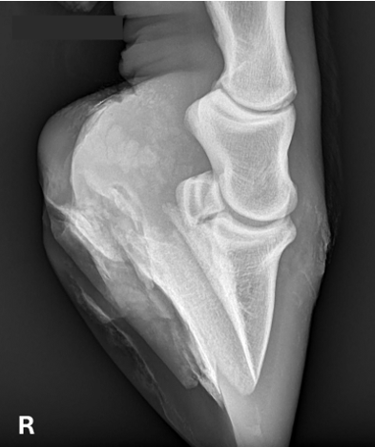

Is uw paard mank, hoefbevangen of is er een vermoeden van een halsprobleem? Dan kan het aangewezen zijn om een radiografisch onderzoek (RX) aan huis uit te voeren. Wij beschikken over een digitaal mobiel radiografietoestel, waardoor opnames eenvoudig bij u ter plaatse kunnen worden gemaakt.

Radiografie (RX)

Consult op de praktijk of aan huis